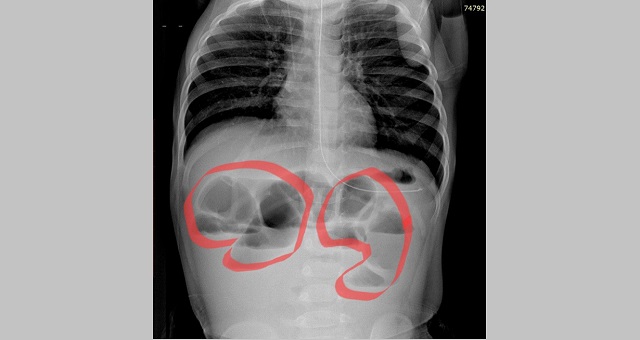

Медики рассказали, что ребенок поступил в приемное отделение с сильными болями в животе, которые появились после поедания нектарина. Рентгеновский снимок брюшной полости показал, множественные уровни жидкости в кишечнике. Это свидетельствовало о кишечной непроходимости.

Врачи приняли решение об экстренном хирургическом вмешательстве. Во время операции хирурги небольшим разрезом рассекли переднюю брюшную стенку и достали расширенный участок кишечника наружу. Он и оказался наполненным крупными частями фрукта.